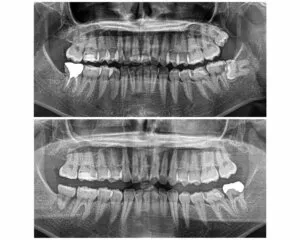

※この写真は、歯牙移植後矯正治療を行い、三年が経過しました。